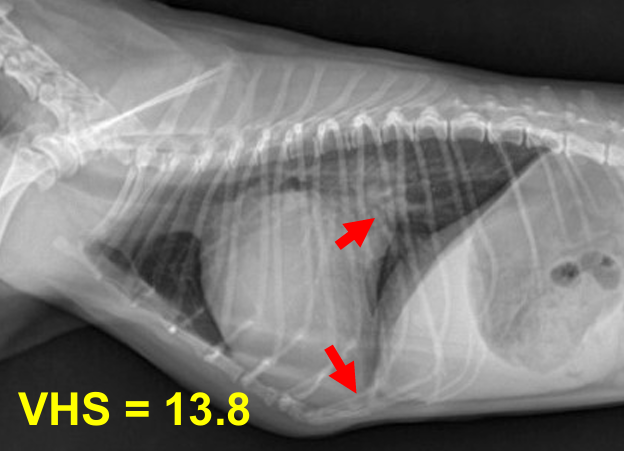

⏺️ MMVD = MVI (Mitral valve insufficiency)

Mitral valve regurgitation, degeneration도 다 같은 말.

Mitral valve (LA-LV 사이) 판막 역류 → 좌심방 혈액량 증가 → 폐정맥 혈액량 증가 → 폐정맥 비대 → 폐도 congestion → 혈액이 혈관을 따라 밖으로 흘러나오면서 폐도 물이 참 → tachypnea, 호흡 곤란, 산소 포화도 감소

1) 1, 2기 : Moderate cardiac remodeling / 3기 : Severe remodeling

| 2기 (Moderate) |

| 기존 소견 동일하게, 1) 심장 커짐 Left auricle 확장, cranial/caudal waist 소실, Globoid heart, Cardiomegaly + Sternal contact 매우 증가 2) 기관 영향 Tracheal elevation, bronchus compression ⇒ Static collapse로 발전 3) 판막, 역류, 심잡음 판막의 thickening (glycose aminoglycan 침착) = Myxomatous degeneration = mitral valve prolapse (MVP, 판막이 뒤로 휨) ⇒ Regurgitation, systolic murmur (심잡음 6단계 중 3단계) 4) 기절 기침 증상이 심하면 syncope (산소 포화도와 혈압이 감소하면서 cardiac output이 감소했기 때문) + interstitial pattern, LA rupture 가능성, 너무 늘어나니 수축이 잘 안 되어 심방부정맥. |